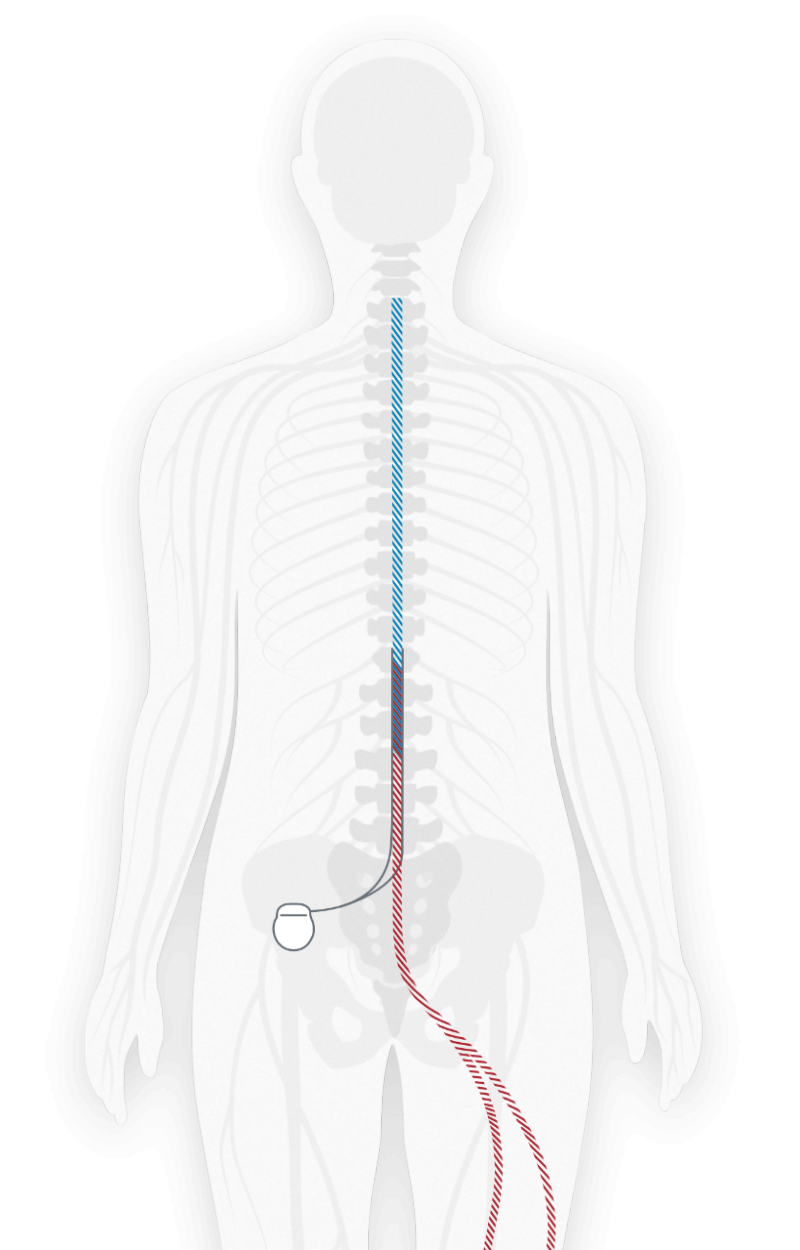

Therapeutic Exercise for Lumbopelvic Stabilization: A Motor。Neuroscience Chapter 13: Spinal Region Flashcards | Quizlet。Correction of Thoracic Hypokyphosis in Adolescent Scoliosis。Amazonで購入した未使用の極美品です。Spinal Cord Stimulation (SCS) For Chronic Pain | Pain.com。自分で取り寄せすると洋書なので輸入に数週間かかると思うので、到着までかなりの日数がかかってしまいます。医学生・研修医のための神経内科学。本商品は東京からの発送なので数日で到着するため、その点良いかと思います。超音波専門医認定試験問題集 第7版。よろしくお願いします。歯科衛生士臨床のすべて。